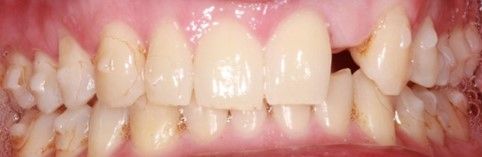

Se presenta un paciente varón de 34 años de edad, no fumador y sin antecedentes médico-quirúrgicos de interés (ASA I), que acudió a la consulta demandando una mejora en la estética de su sonrisa.

El paciente presentaba una agenesia congénita en el incisivo lateral superior izquierdo que había sido tratada previamente con ortodoncia para cerrar dicho espacio.

Tras el examen intraoral del paciente y el estudio radiográfico, se plantea la opción de tratamiento de abrir nuevamente el espacio mediante ortodoncia para rehabilitar la ausencia con un implante de circona, asegurando la estética que demandaba el paciente.